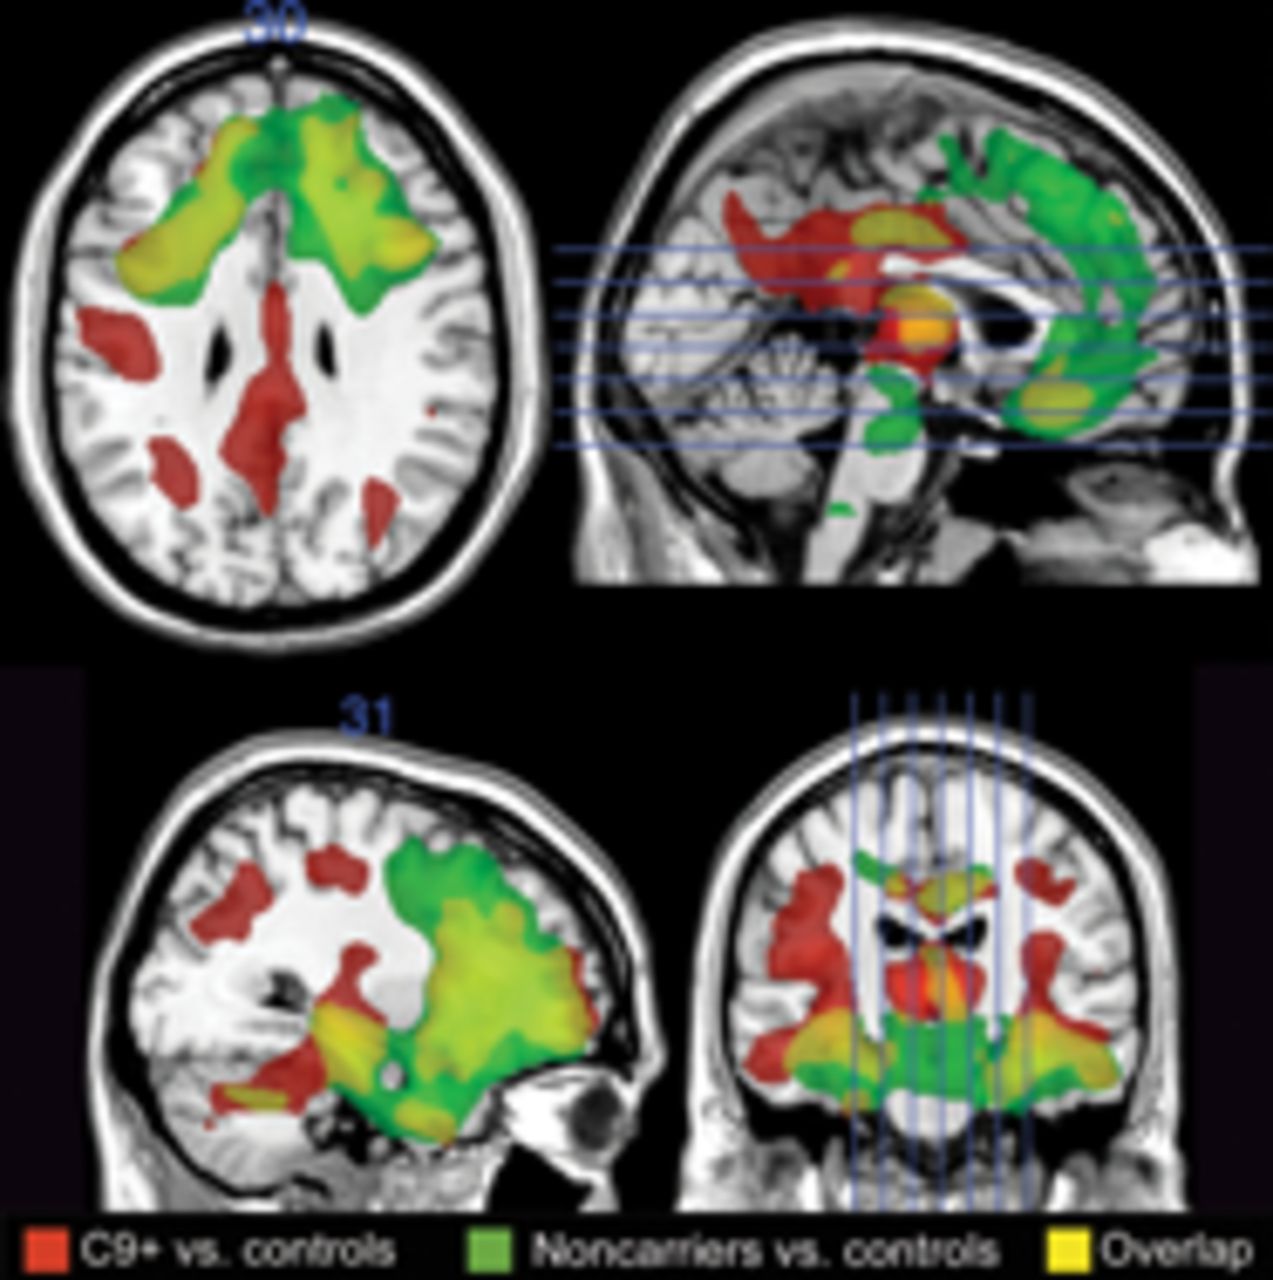

额颞叶痴呆由于C90RF72突变:临床和成像特性

的C9ORF72额颞叶痴呆的重复扩张是一种相对常见原因(FTD),特别是在患者FTD-amyotrophic侧索硬化症(ALS),精神功能,和一个强大的家族病史。患者的C9ORF72hexanucleotide重复扩张也开发行为变异FTD, ALS,或者FTD-motor神经元疾病相似的临床和影像特征。